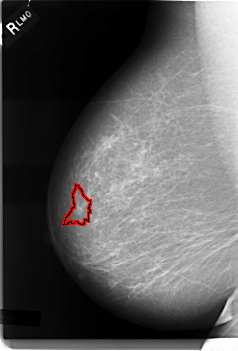

C_0003_1.RIGHT_MLO

RIGHT_MLO LINES 5960 PIXELS_PER_LINE 4032 BITS_PER_PIXEL 12 RESOLUTION 50 OVERLAY

FILE: C_0003_1.RIGHT_MLO.OVERLAY

TOTAL_ABNORMALITIES 1

ABNORMALITY 1

LESION_TYPE MASS SHAPE IRREGULAR MARGINS SPICULATED

ASSESSMENT 5

SUBTLETY 4

PATHOLOGY MALIGNANT

TOTAL_OUTLINES 1

BOUNDARY